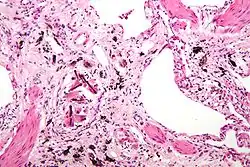

| Micrograph of asbestosis (with ferruginous bodies), a type of pneumoconiosis. H&E stain. | |

Pneumoconiosis is the general term for a class of interstitial lung disease where inhalation of dust (for example, ash dust, lead particles, pollen grains etc) has caused interstitial fibrosis.[1][2] The three most common types are asbestosis, silicosis, and black lung disease.[3] Pneumoconiosis often causes restrictive impairment,[4] although diagnosable pneumoconiosis can occur without measurable impairment of lung function.[1][2] Depending on extent and severity, it may cause death within months or years, or it may never produce symptoms. It is usually an occupational lung disease, typically from years of dust exposure during work in mining;[5] textile milling; shipbuilding, ship repairing, and/or shipbreaking; sandblasting; industrial tasks; rock drilling (subways or building pilings);[6] or agriculture.[7][8] It is one of the most common occupational diseases in the world.[9]